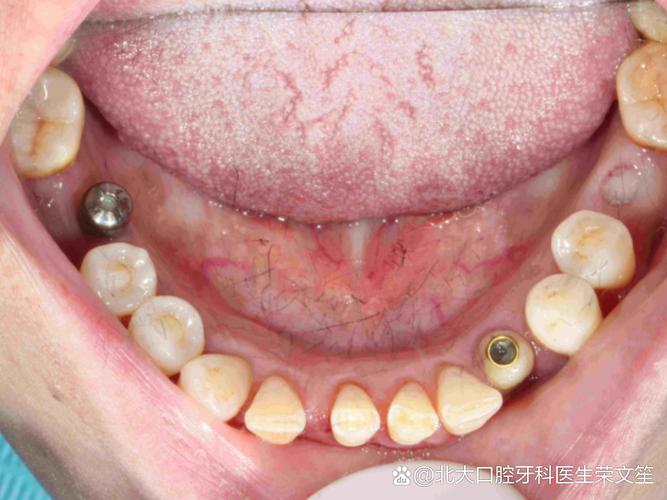

种植牙的成功,离不开精准的影像检查,现代口腔种植常用的影像技术包括根尖片、曲面断层片及锥形束CT(CBCT),其中CBCT因三维成像、高分辨率、辐射剂量可控等优势,已成为种植术前的“金标准”,拍片的核心作用体现在以下方面:

定位重要解剖结构,规避手术风险

CBCT能清晰显示下牙槽神经管、上颌窦底、颏孔、鼻腭管等解剖结构的位置及走行,下颌后牙区的种植体需距离下牙槽神经管至少2mm,上颌后牙区的种植体需距离上颌窦底至少1mm,CBCT可帮助医生精准标记安全植入范围,避免神经损伤和上颌窦穿孔,对于邻牙牙根倾斜、弯曲的情况,CBCT可明确牙根形态,确保种植体与牙根间保持足够距离(至少1.5mm)。

术前要求查看影像报告,参与方案设计

正规种植前,医生应向患者展示CBCT影像,解释牙槽骨情况、重要解剖结构位置及种植方案,患者可主动询问:“我的骨量够吗?种植体离神经有多远?是否需要植骨?”等,确保对治疗方案有充分了解。